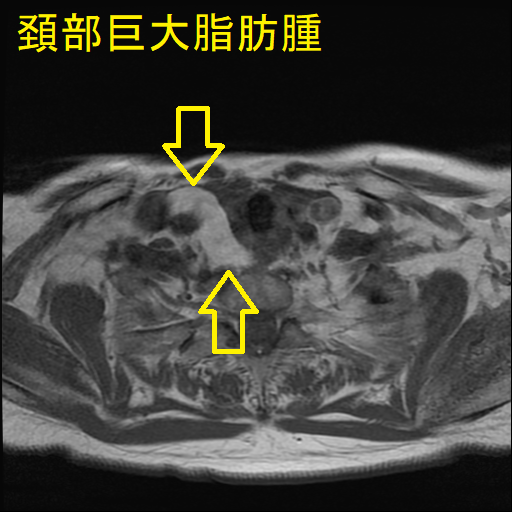

巨大頚部脂肪腫